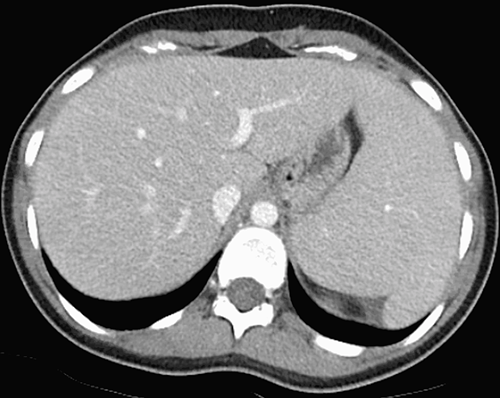

腹部CT

检查发现脾脏轻度增大,其余未见异常(图1)。

(图1 腹部CT检查显示脾肿大,余未见异常)